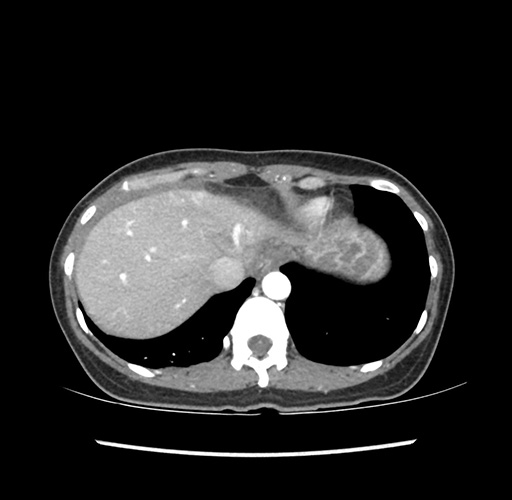

Imaging Analysis

Look through the patient's CT scan to identify any areas of concern for the necessary procedure.

Based on your CT findings, which issue(s) would give reason for "planned slowing down moment(s)" in this case?

Considering a standard left lateral sectionectomy procedure, what step(s) of the operation would you do differently in this case ?